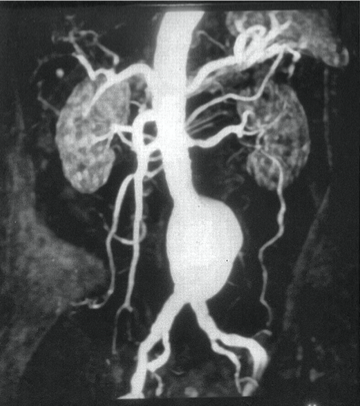

What does this angiogram refer to

Aortic Aneurysm

What does this CT angiography refer to

Aortic aneurysm